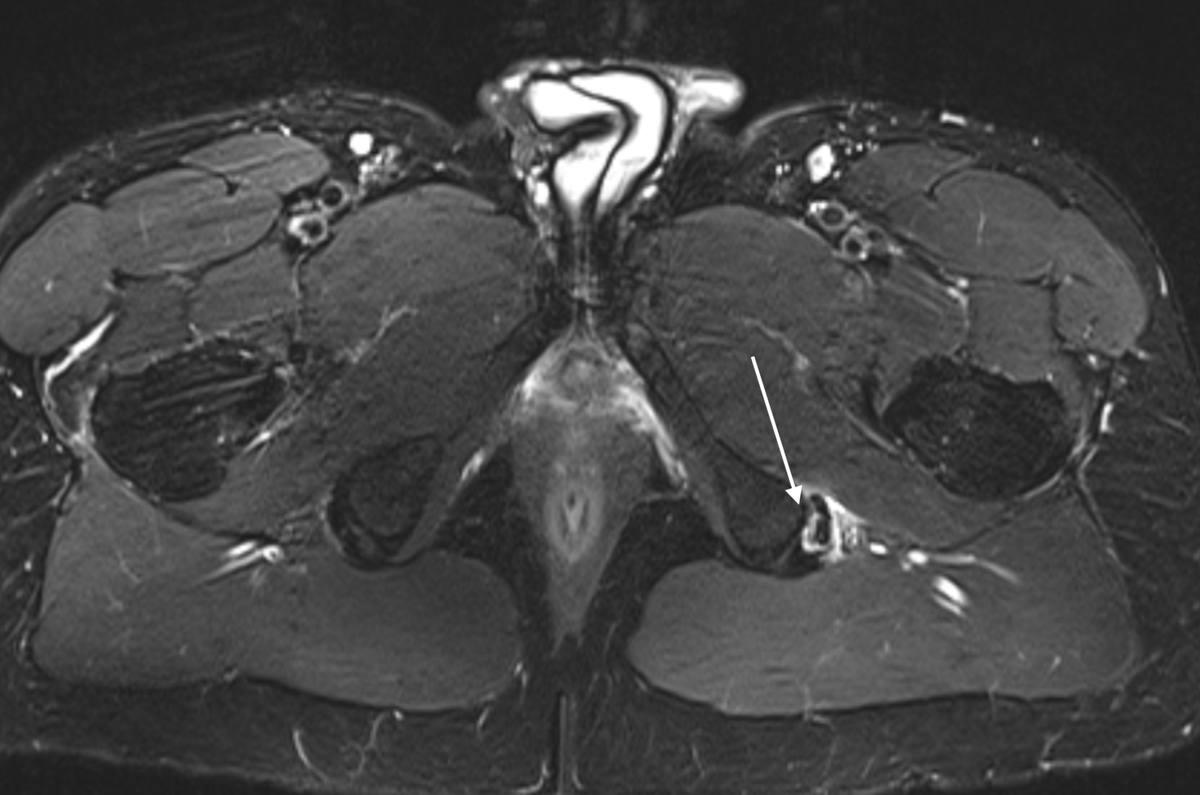

@northwoods1980 @DrDerekOchiai Subtle with a capital S.

If you looked at 100 high level athletes, this fem-head neck junction would be one of the most “normal” you could find.

#HipArthroscopy is a phenomenon tool to treat #HipFAI. When I do a cam FAI correction, the goal is to eliminate the impingement and make a normal hip shape, and not over-resect the femur. An optimal osteoplasty should just look like a normal hip.